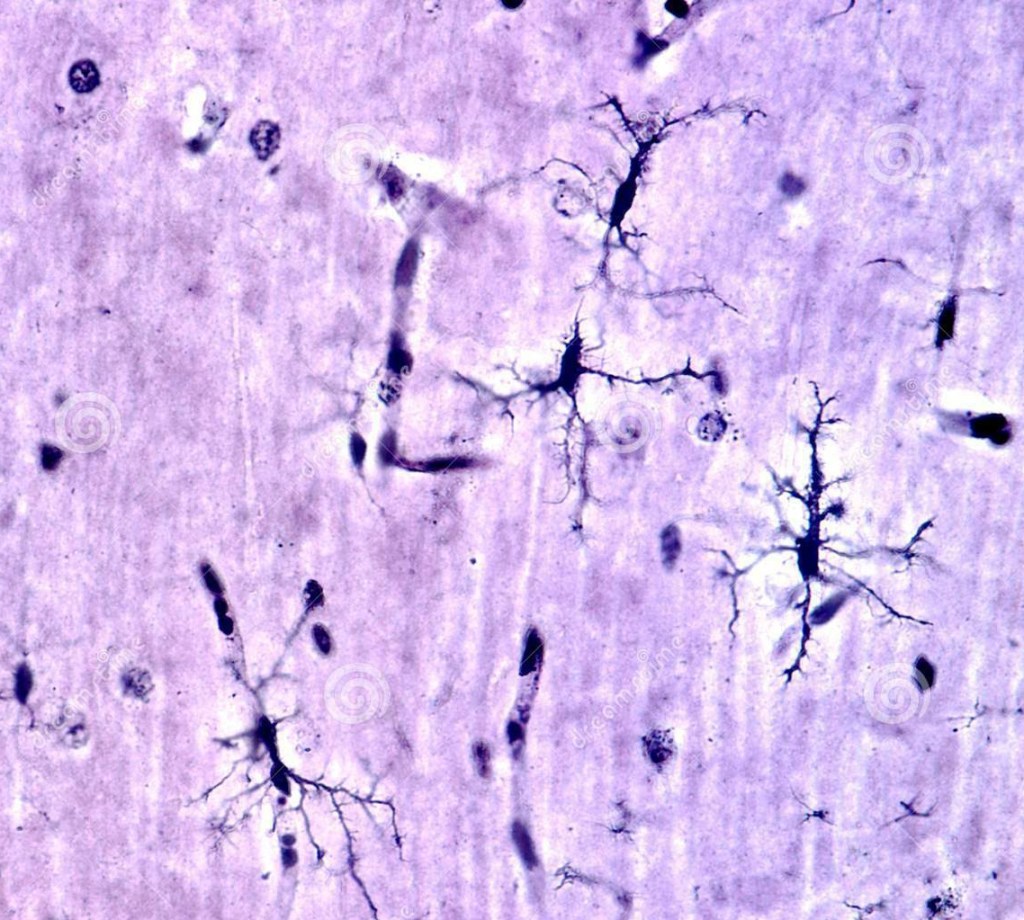

Yaddaş nədir? Yaddaş, müxtəlif anatomik quruluşların (amigdala, hipokampus, prefrontal korteks) bir-biri ilə əlaqəli işlədiyi, görmə, eşitmə və məkan məlumatları kimi müxtəlif növ məlumatları duyğu orqanlarımızla əlaqələndirib istifadə edə biləcəyimiz kompleks bir sistemdir. Yaddaşın üç əsas funksiyası olduğu düşünülür: Kodlama (Encoding): Duyğu orqanları tərəfindən alınan məlumatların saxlanıla bilməsi üçün işlənməsidir. Saxlama (Storage): Məlumatın müəyyən bir müddət ərzində depoda saxlanılmasıdır. Xatırlama ( Retrieval) : istifadə edilə bilməsi üçün saxlama sahəsindən məlumatların alınmasıdır, buna geri çağırılma da deyilir. Bundan əlavə, yaddaşın fərqli xüsusiyyətlərini nəzərə alaraq bir neçə sinifə bölmək olar: